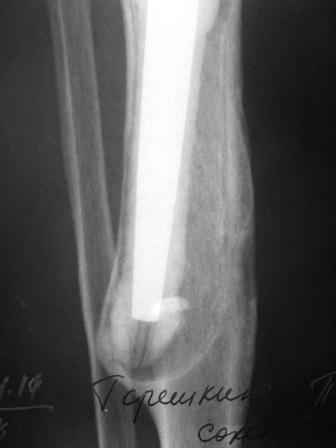

Уважаемые коллеги!Хотелось бы услышать Ваше мнение о возможности и способе помощи больной. 1939 г.р. В 1995г. эндопротезирование правого коленного сустава протезом Феникс, в 1999г. в г. Томске - ревизия - ротационный хинч W.Link. C 2005г. прогрессирует варусная деформация за счетнестабильности тибиального компонента. Попытка ортезирования - без эффекта. Попытка направить в ФСМУ без эффекта, да и больная не хочет никуда ехать.С уважением, Leonid

Технически можно надеть гвоздь на ножку протеза

Понятно что для решения на операцию артродеза необходимы веские причины. Но я не уверен что здесь асептическое расшатывание. Судя по снимкам, бедренный компонент стоит не плохо, и есть рассасывание костной ткани вокруг всего протеза в голени. Что-то мне подсказывает об инфекционном процессе, возможно вялотекущем. В наших условиях я сделал бы обследование включающее анализы крови с СОЭ, СРБ. Сделал бы пункцию коленного сустава или даже биопсию мягких тканей для посева и микроскопии.